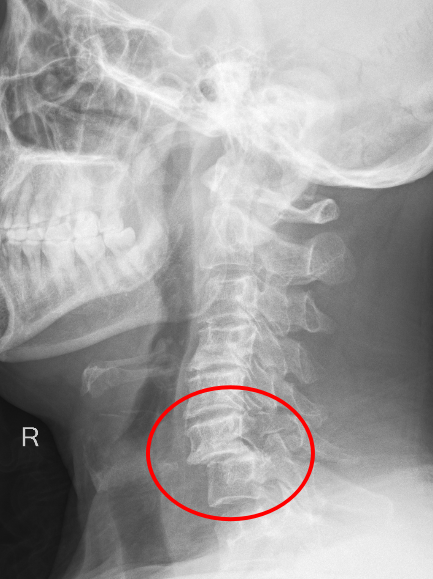

患者朱先生因意外從高處墜落,頸部劇痛、四肢麻木無(wú)力,急診入院后經(jīng)CT及MRI檢查確診為第6頸椎骨折脫位伴脊髓損,隨時(shí)可能引發(fā)呼吸衰竭或永久性癱瘓。傳統(tǒng)保守治療風(fēng)險(xiǎn)極高,骨科主任彭李華主任醫(yī)師及脊柱專(zhuān)業(yè)組長(zhǎng)張利強(qiáng),迅速組織多學(xué)科會(huì)診,結(jié)合國(guó)際最新指南與患者個(gè)體情況,果斷制定“前路頸椎間盤(pán)切除+植骨融合內(nèi)固定術(shù)”方案,以微創(chuàng)技術(shù)最大限度減少神經(jīng)損傷,脊髓受壓明顯減輕,重建頸椎穩(wěn)定性。

術(shù)后影像顯示,頸椎序列完美復(fù)位,內(nèi)固定位置精準(zhǔn),患者次日即感雙上肢麻木緩解,肌力較術(shù)前明顯改善,術(shù)后第二天,患者頸部及雙上肢疼痛癥狀消失,在頸托保護(hù)能自主下床行走,術(shù)后一周痊愈出院。